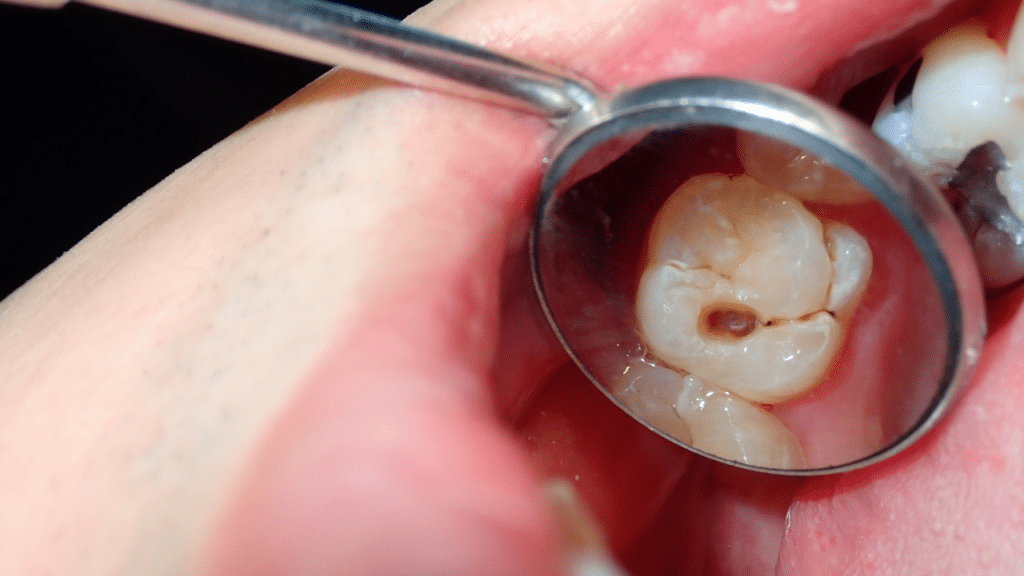

A dental filling is a straightforward restorative treatment designed to repair a tooth affected by decay or a minor fracture. Once the weakened area is carefully removed, the tooth is thoroughly cleaned and sealed with a strong, durable material to prevent bacteria from causing further damage.

Often, early decay is symptomless, which is why regular check-ups are vital. You may need a filling if you experience sensitivity to hot or cold, or if the dentist discovers a cavity during an exam or on an X-ray. We always explain the findings clearly before starting treatment.